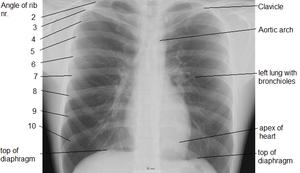

Landmarks

In the average person, the diaphragm should be intersected by the 5th to 7th anterior ribs at the mid-clavicular line, and 9 to 10 posterior ribs should be viewable on a normal PA inspiratory film. An increase in the number of viewable ribs implies hyperinflation, as can occur, for example, with obstructive lung disease or foreign body aspiration. A decrease implies hypoventilation, as can occur with restrictive lung disease, pleural effusions or atelectasis. Underexpansion can also cause interstitial markings due to parenchymal crowding, which can mimic the appearance of interstitial lung disease. Enlargement of the right descending pulmonary artery can indirectly reflect changes of pulmonary hypertension, with a size greater than 16 mm abnormal in men and 15 mm in women.[6]

Appropriate penetration of the film can be assessed by faint visualization of the thoracic spines and lung markings behind the heart. The right diaphragm is usually higher than the left, with the liver being situated beneath it in the abdomen. The minor fissure can sometimes be seen on the right as a thin horizontal line at the level of the fifth or sixth rib. Splaying of the carina can also suggest a tumor or process in the middle mediastinum or enlargement of the left atrium, with a normal angle of approximately 60 degrees. The right paratracheal stripe is also important to assess, as it can reflect a process in the posterior mediastinum, in particular the spine or paraspinal soft tissues; normally it should measure 3 mm or less. The left paratracheal stripe is more variable and only seen in 25% of normal patients on posteroanterior views.[7]